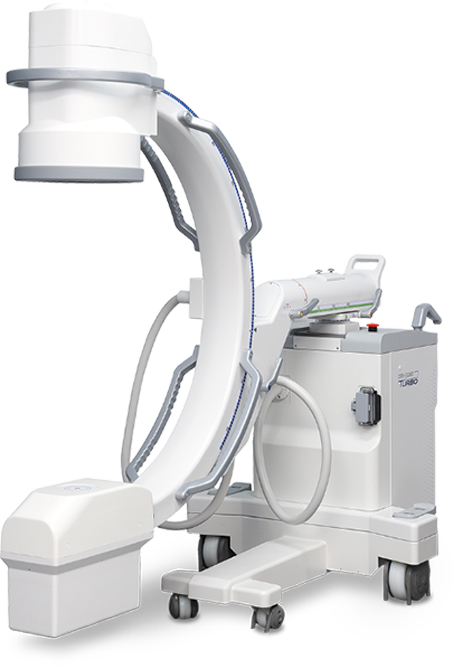

C-ARM

ZEN-2090 TURBO

비수술 신경치료 특수 영상장치

컴퓨터 특수 X-ray 영상장비인 C-arm은 정밀한 주사치료를

위한 기기로, 뼈와 관절 등을 실시간 Full HD 화면으로 투시하여

병변의 원인 위치를 확인할 수 있습니다. 아주 가는 신경까지도

정밀하게 탐지할 수 있어, 높은 정밀도를 가진 시술이 가능합니다.